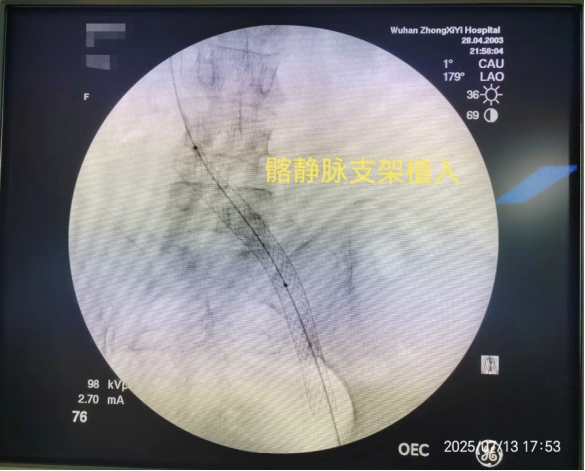

第二步:等到患者可安全抗凝后,再使用球囊扩张狭窄的髂静脉并植入支架,从根本上解决“血管狭窄”的问题。

术后,李阿姨的左腿肿胀当即消退,近日复查显示血栓已完全清除,恢复非常顺利。